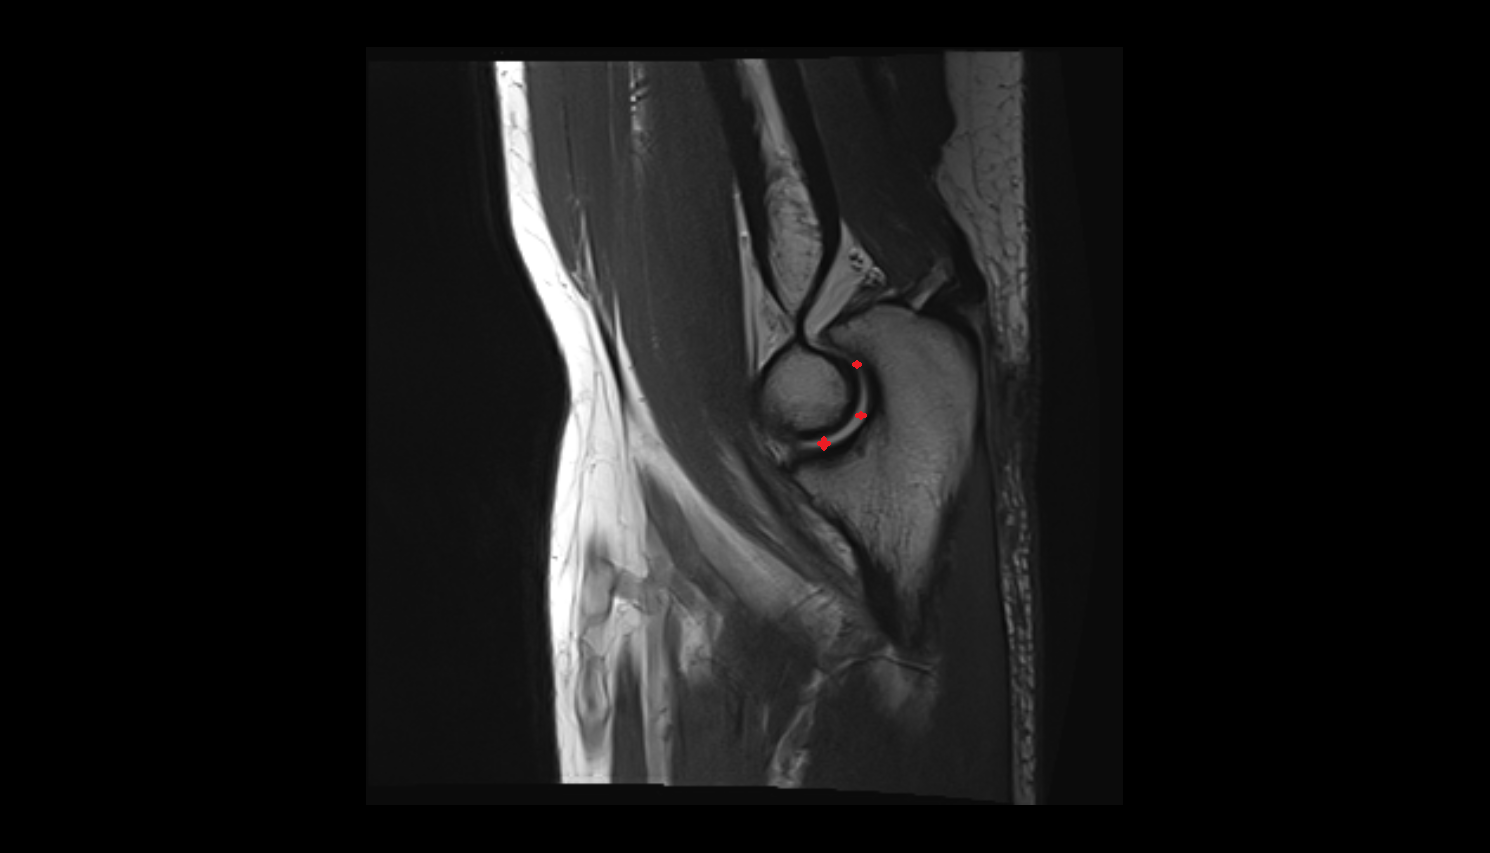

- Knee Joint